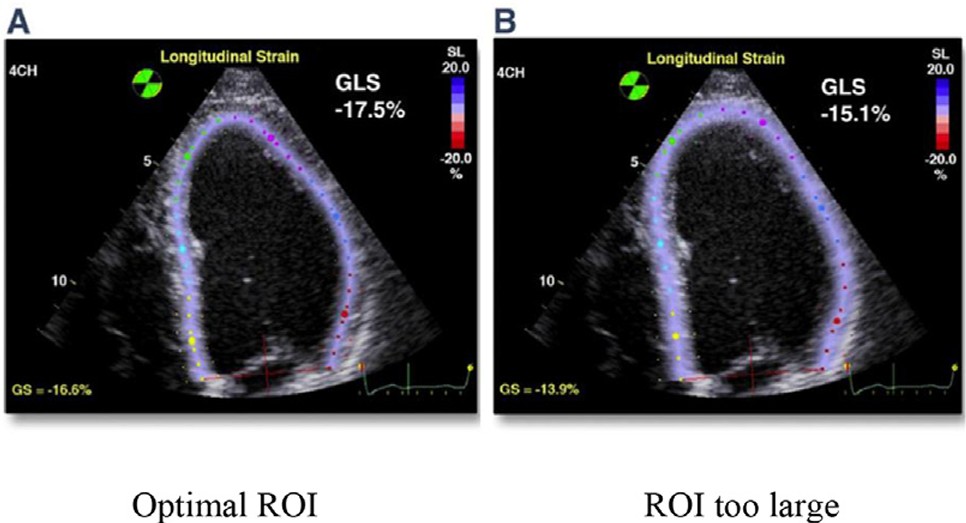

(3) Ajuste da ROI deve evitar um aumento excessivo de sua largura, pois pode subestimar os valores do strain. Apenas a parede miocárdica (por completo) deve ser contemplada no ajuste, devendo evitar a inclusão do pericárdio.

(4) Por outro lado, uma ROI pequena pode superestimar os valores do strain. Tal fato merece especial atenção naqueles casos de hipertrofia miocárdica e o ajuste deve ser feito criteriosamente ou a ROI refletirá apenas a deformação da camada subendocárdica.